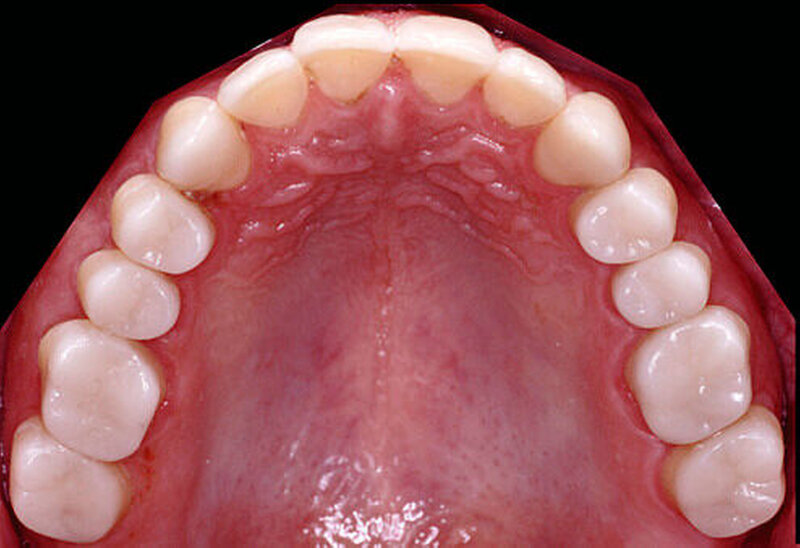

Nach einer klinischen Funktionsanalyse (Abbildungen 1 und 2) werden Situationsmodelle hergestellt und diese anhand einer arbiträren Scharnierachsbestimmung und eines Zentrikregistrats im Artikulator montiert. Die für die spätere Versorgung funktionell und ästhetisch ideale Vertikaldimension wird durch ein analytisches Wax-up eingestellt (Abbildung 3). Dieses wird in eine diagnostische Schablone (Tiefziehfolie) für eine „ästhetische Evaluierung“ durch den Zahnarzt und den Patienten überführt. Dazu kann die Schablone mit niedrigviskösem Komposit gefüllt und reversibel auf die mit flüssiger Vaseline isolierten Zähne gesetzt werden. Findet dieser Restaurationsvorschlag die Zustimmung des Patienten, wird im zahntechnischen Labor eine in der Höhe und in der Bisslage dem Wax-up entsprechende Repositionsschiene mit Front-Eckzahn-Führung angefertigt. Diese Schiene sollte circa drei Monate möglichst permanent getragen werden. Diese „funktionelle Evaluierung“ dient dazu zu prüfen, ob der Patient die neue Bisslage beschwerdefrei toleriert [Edelhoff et al., 2013; Harper, 2000; Rivera-Morales et al.,1992].